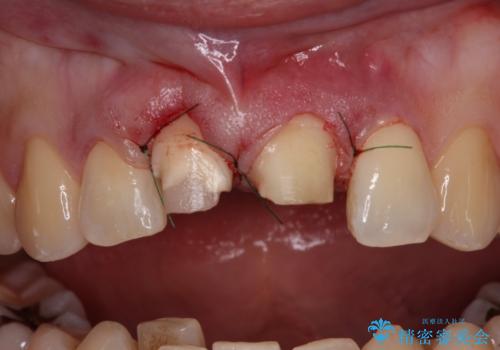

失活した歯は、根管治療を行った後に部分矯正により歯根を引っ張り出し、歯周外科処置により左右の歯肉の位置が揃えることとしました。

強い衝撃を受けた歯であるため、定期的にレントゲン撮影を行い、歯根吸収が起きていたり、神経が失活していたりしないか確認を行い、ある程度安定したところでオールセラミッククラウンにて補綴治療を行うこととしました。